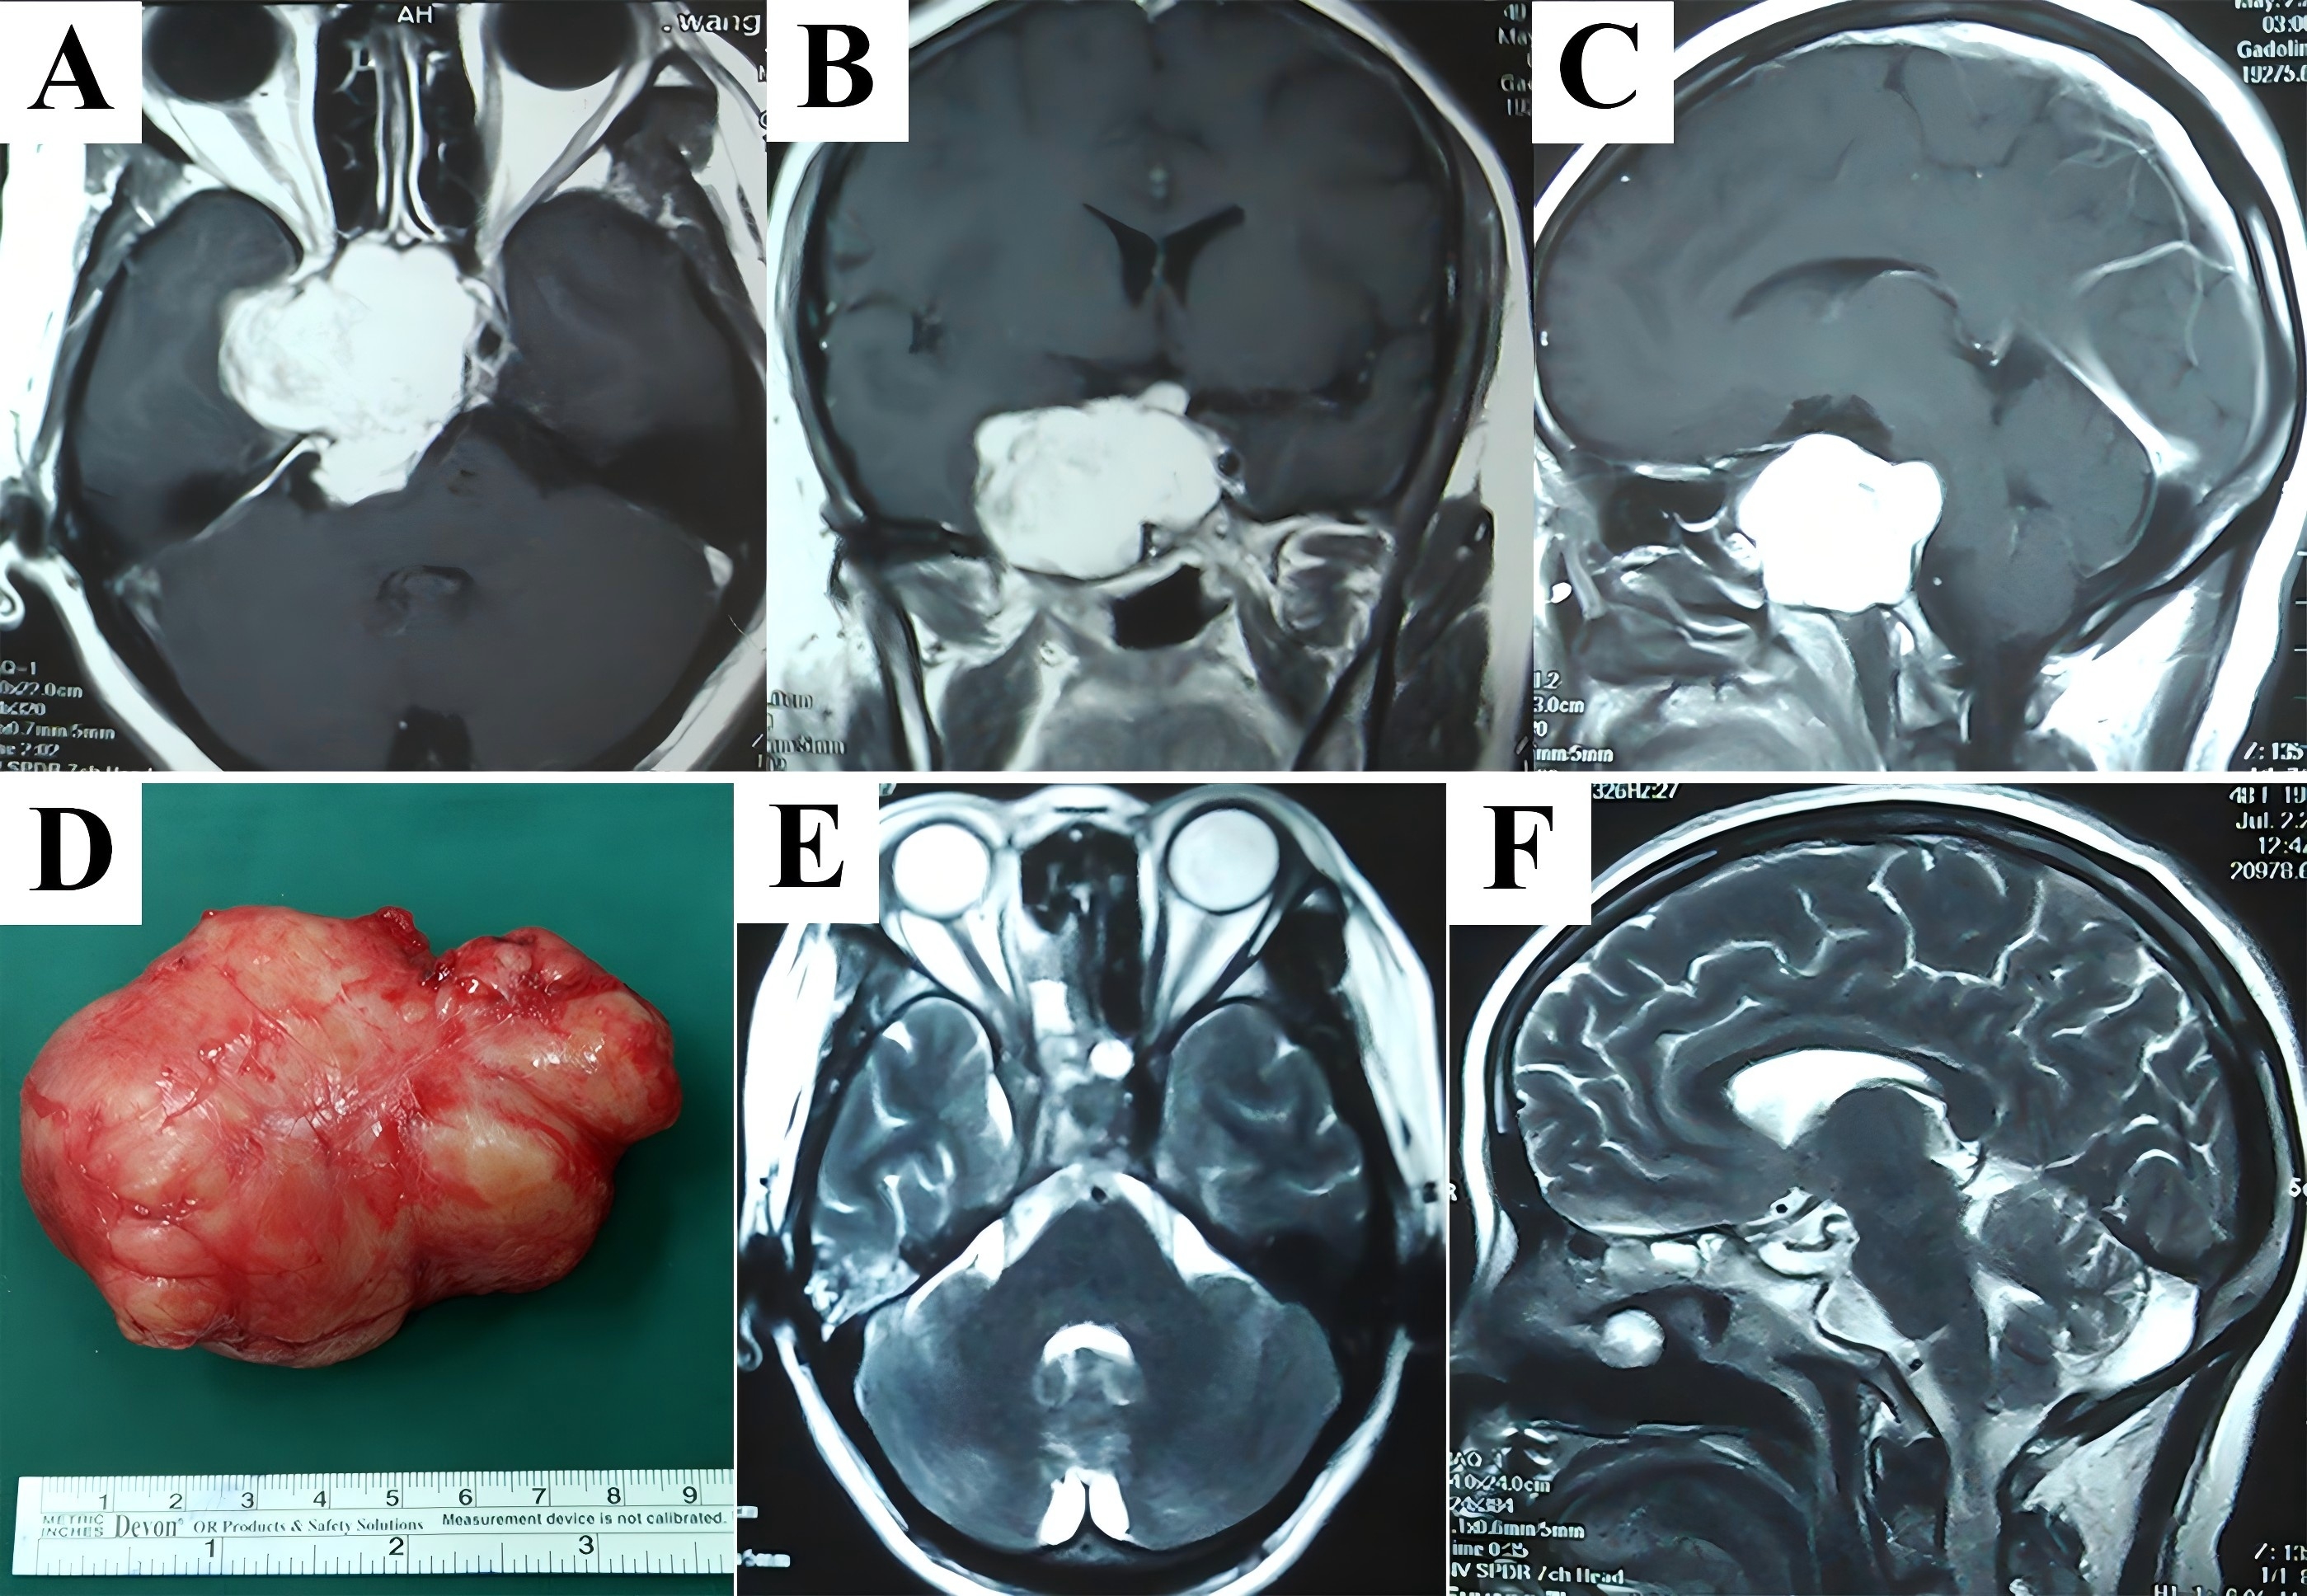

A 59-year-old man received transcranial surgery for skull base schwannoma 5 years ago. Although pathological examination found tumor exhibiting characteristics of active proliferation, he did not undergo postoperative radiotherapy. The major complaints for which he sought medical help included blurring, ptosis, limitation of extraocular movements. An extensive tumor occupying the parasellar area, Meckel’s cave, temporal fossa, PPF, ITF, and parapharyngeal space was depicted in contrast T1-weighted MRI (Fig. 4A-C). The maxillary swing approach was selected, which could provide enhanced lateral exposure of the tumor that predominantly allocated within extracranial space. The recurrent tumor firmly adhered to the adjacent tissues and challenged the dissection planes. Under direct visualization, not only stripping of tumor from lateral wall of the CS in a single piece but confirmation of intact dura and negative margins by intraoperative fresh-frozen sectioning were performed to obtain local disease control (Fig. 4D). Postoperative MRI showed total resection of the tumor (Fig. 4E&F). The patient developed trismus and palatal fistula after surgery. He wore the obturator dental plate to facilitate swallowing, and the majority of the fistulae shrunk with time accompanied by improvement of the trismus. The patient who had a definitive histological diagnosis of the malignant peripheral nerve sheath tumor (MPNST) (WHO Ⅲ) refused to receive adjuvant radiotherapy. Fortunately, no locoregional tumor recurrence was observed after a period of 129 months.

Figure 4. Recurrent MPNST (WHO Ⅲ) allocated in the skull base were completely resected via maxillary swing approach. A large and extensive tumor occupying multiple compartments including the parasellar area, Meckel’s cave, temporal fossa, PPF, ITF, and parapharyngeal space as depicted in axial (A), coronal (B), and sagittal (C) contrast T1-weighted MRI exhibited heterogeneous enhancement due to necrosis or cystic degeneration. The patient experienced tumor resection in a piecemeal fashion before admission to our hospital. In contrast, following reflection of the maxilla, we identified and removed the recurrent tumor as a whole (D). Postoperative MRI confirmed total removal of the tumor (E, F). MPNST, malignant peripheral nerve sheath tumor; PPF, pterygopalatine fossa; ITF, infratemporal fossa; MRI, magnetic resonance imaging.